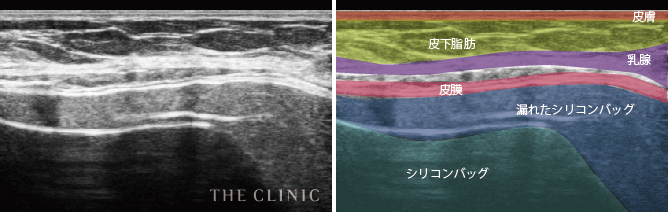

- シリコンバッグが破損して、被膜内へのシリコンの漏出が認められます。場合によっては、被膜外へ漏れ出すこともあります。

また、内容物が漏出していた場合はそれらをすべて洗浄して除去する必要があります。ただし、触診だけでは漏出範囲は分からないので、洗浄する際に内容物が残ってしまう可能性があります。こうならないためにも、抜去前に破損状況やバッグ内容物の漏出具合を超音波エコーやMRIなどで検査することが重要です

シリコンバッグによるシリコンバッグの破損のエコー診断カルテ